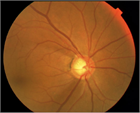

1. 定期レビューを行い、典型的な原発開放隅角緑内障の症例について画像を用いて解説した。

1. 早期発見していれば生涯保たせられたかと悔やむ症例であった。角膜厚が薄いため眼圧は過小評価されていると考えて、より低い眼圧を目標とした。詳細については本文を参照されたい。